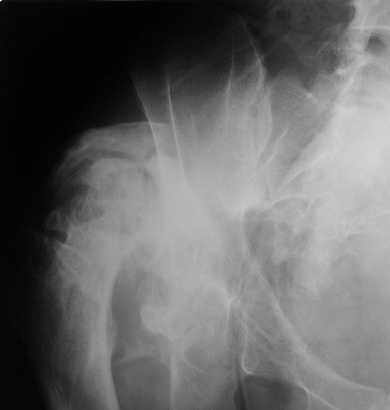

Уважаемые коллеги. Пациент 30 лет 3 года назад в результате травмы получил травматический дефект нижних конечностей до в/3 голеней, был пропущен вывих бедра.

В настоящее время очень неплохо ходит на протезах, движения в неоартрозе близки по объему к здоровой стороне. Основная жалоба - выраженная боль при ходьбе. планируем двухэтапное эндопротезирование - задним доступом мобилизовать проксимальный отдел бедра, резецировать шейку, аппаратом низвести бедро(головку оставить там где она есть, так как больших дефектов не видно(может пригодится в последующем?)). Вторым этапом бесцементное эндопротезирование. Насколько такой вариант реалистичен? Доступ для второго этапа? Может быть другие варианты?С уважением, Максим

На последнем срезе КТ задний край практически отсутсвует по сравнения со здоровой стороной. Разумеется, что это плоскостное изображение, но головка вывихнулась не только в плоскостную щель захваченную на КТ. Если вы считаете, что удастся установить туда чашку даже низкопрофильную, остается пожелать вам успехов. Но перед этим можно смоделировать установку чашки на скиаграммах КТ.

За пожелание успехов - спасибо, думаю это пригодится, не очень понял про плоскостную щель, специально предоставил срезы на уровне свода - он цел, дефект заднего края ниже, за счет заглубления он будет еще меньше, по данным 3d - должно получиться.

Низводить надо обязательно, лучше в аппарате и лучше без остеотомии.

Если в аппарате низводиться не будет, то из небольшого доступа, лучше под контролем С-дуги выполнить остеотомию шейки. Без предварительного

низведения максимально возможная коррекция длины - 2,5-3 см.

Решение по ВВ придется принимать по месту.... Сумеете "подрыться" и получить хорошее покрытие чашки (+2 винта об-но) - хорошо, если нет -

костная аутопластика из головки.